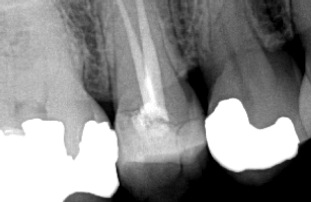

DIGITAL RADIOGRAPHS

Dental radiographs taken at your dental office are used to look for dental decay and to better view restoration margins. The radiographs we take at Westside Endodontics are done at different angles (than the ones taken at your dental office) to allow better visualization of overlapping roots. This is why we may require additional radiographs, even though it seems your dentist already took images of the same tooth.

We use digital imaging at Westside Endodontics, which has much less exposure time than traditional radiographs, resulting in 80% less radiation exposure to our patients. Digital images are also easier to store and transfer (when needed).